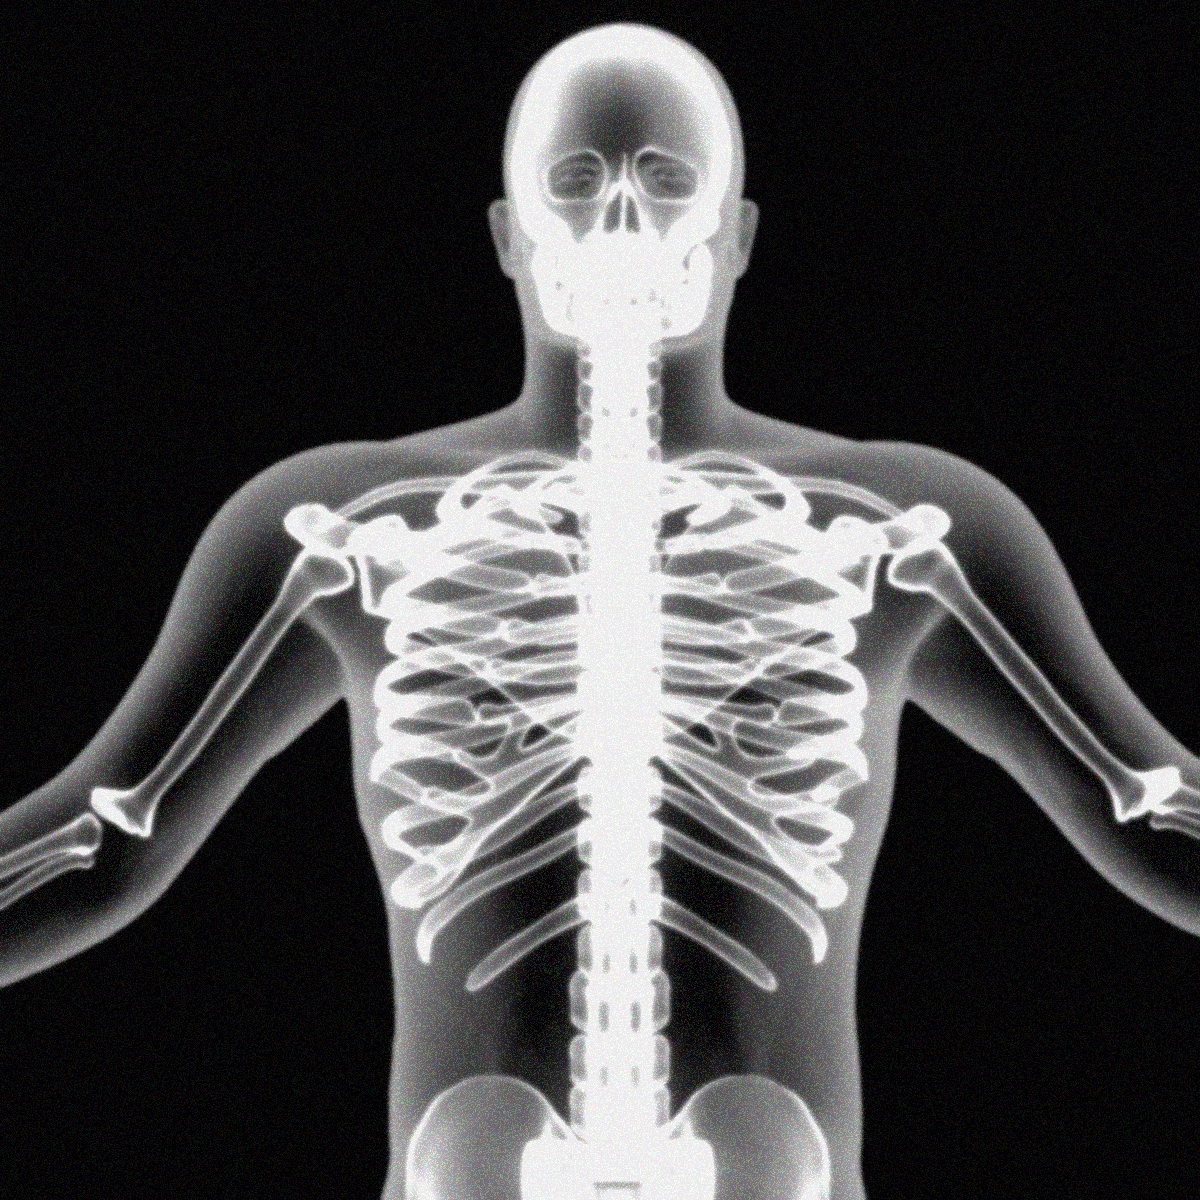

human full chest bone

The Human Body By X-rays On Blue Background. Stock Illustration …

Rising body – x-ray stock illustration. Illustration of skull – 15436323

What Are X-rays | Inside Our Body | DK Find Out